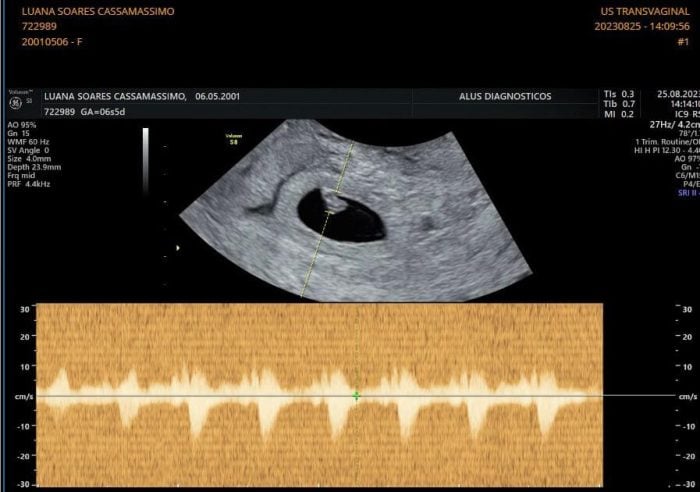

Ver nossa bebê e ouvir o coraçãozinho dela pela primeira vez me inundou com um amor imenso. Tenho comemorado todos os dias essa vidinha dentro de mim, sinto que preciso sempre vibrar esse presente que chegou para a gente. A Cecília está prevista para abril de 2024!